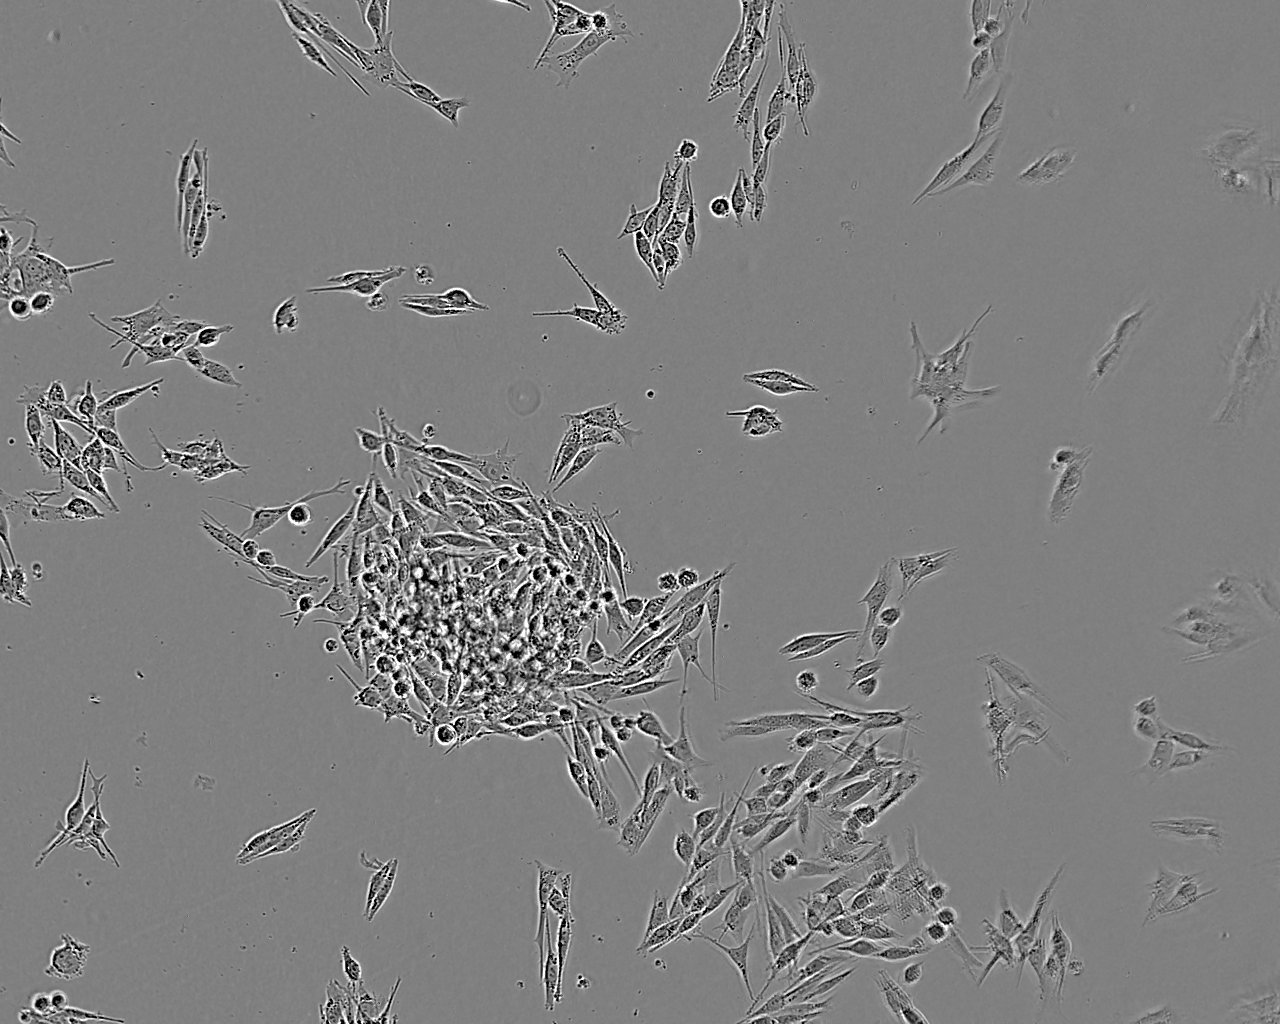

特征特性 从一例原位脉络膜黑色素瘤病例中分离建系。该细胞是ESTDAB计划中收集的超过170株黑色素瘤细胞中的一株

形态特征 上皮细胞样

生长特征 贴壁